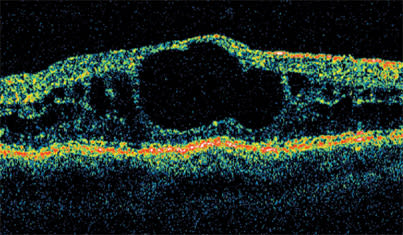

Laser treatment becomes less effective when cysts are present, as in this case of diabetic cystoid macular edema.

Another characteristic that we look for in DME is the presence of cysts. When cysts develop in the macula, laser treatment becomes less effective. Steroids or anti-VEGF agents are usually a better treatment choice. Over time, cysts coalesce and become larger and larger. The larger they become, the less likely it is that treatment will improve visual acuity, even when the retinal anatomy is normalized.